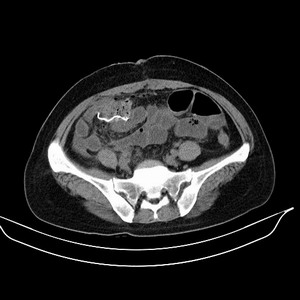

女 42岁 子宫肌瘤于外院术后两天,感腹胀。x线提示肠梗阻。

子宫肌瘤于外院术后两天,出现肠扭转梗阻,很明显。但右下腹部出现的线状高密度,是什么呢?有什么手术会有这样的物品呢?不会把电刀的导线遗留在腹腔吧!?

结果:术后纱布遗留,术后麻痹性肠梗阻肠梗阻

上面的图像是我们从手术室拿来的纱布做了个ct平扫,发现纱布里确实存在有一条致密影。后得知致密影是为防止手术时纱布遗留而设计。关腹时怀疑纱布遗留可做个床边透视或拍片可明确。